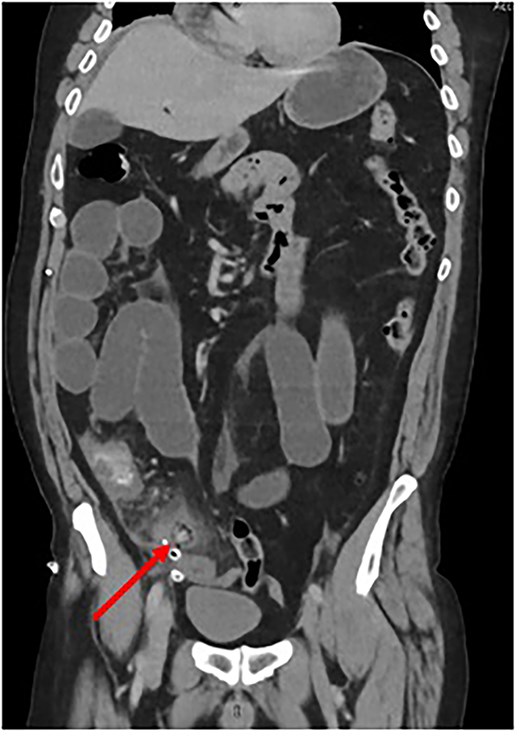

In the postoperative period, the patient developed an ileus. To exclude a mechanical cause of bowel obstruction, a contrast-enhanced CT abdomen-pelvis was performed. This confirmed an ileus but also reported a ‘Persisting blind ending tubular structure extending from caecum inferior and medially’ and “intraluminal free gas consistent with necrosis” (Fig. 1). Conclusion by the radiologist stated that appearances were consistent with “ongoing appendicitis.”

Coronal CT scan depicting Surgicel® as a tubular structure containing gas. (Created by authors)